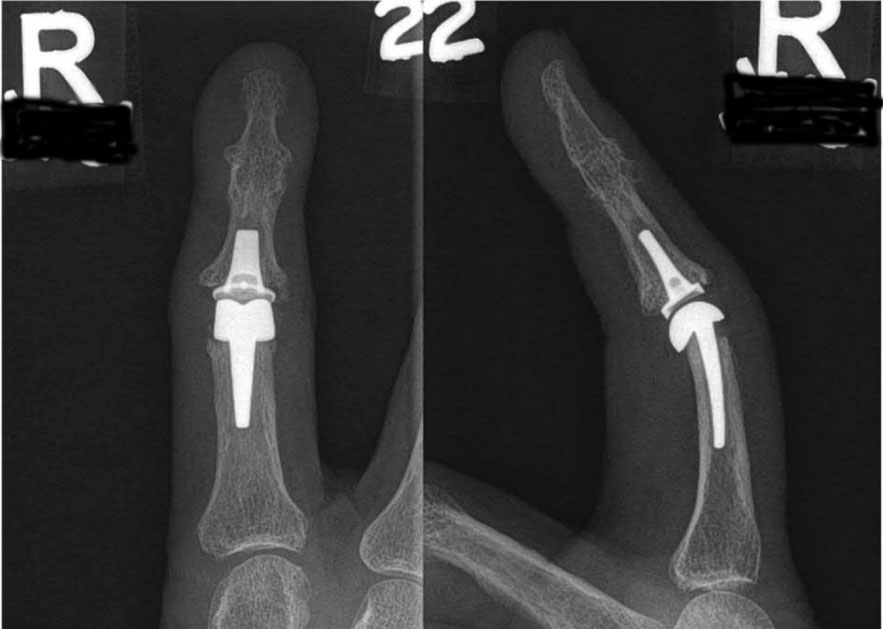

X-ray of patient with severe arthritis of the fingers

X-rays of a patient with severe arthritis of the PIP joint of the index finger.

Reproduced from Carlson Strother C, Moran S, Rizzo M. Small Joint Arthroplasty of the Hand: An Update on Indications, Outcomes, and Complications. J Am Acad Orthop Surg 2023;31:793-801.

Post-operative X-rays of patient with severe arthritis of the index finger PIP joint

X-rays after the patient underwent replacement of the index finger PIP joint with a metal-on-plastic (polyethylene) implant.